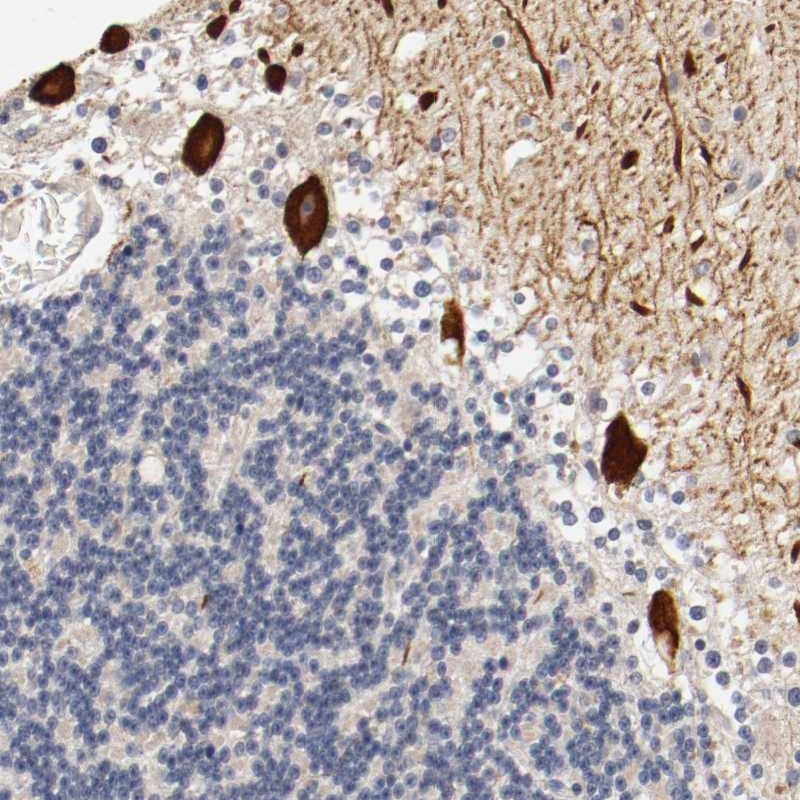

- Experimental details

- Immunohistochemical staining of human cerebellum shows strong cytoplasmic positivity in purkinje cells.

- Validation comment

- Staining pattern consistent with experimental and/or bioinformatic data.